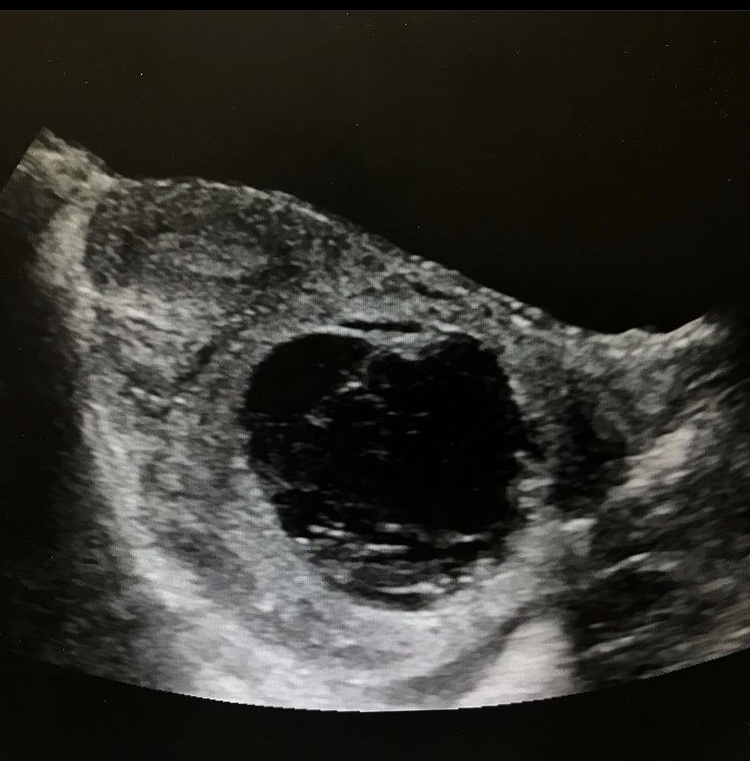

Case #2

1 yo female with right ovarian torsion